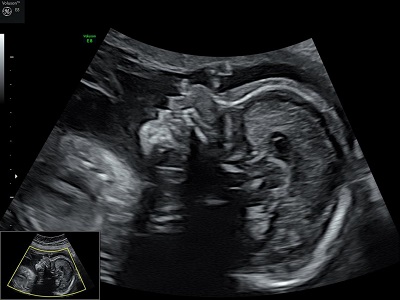

"Voir ce qui est invisible, grâce à des sons inaudibles."

En tant que profession médicale, nous pouvons pratiquer toutes les échographies de dépistage au cours de la grossesse, ainsi que les échographies pelviennes (gynécologiques), après l'obtention d'un diplôme inter-universitaire d'échographie obstétricale et gynécologique.

Nous utilisons pour réaliser nos examens un échographe performant, le Voluson E8 de chez General Electric. Ainsi, il n'est plus nécessaire de boire beaucoup d'eau avant une échographie.

Nous réalisons les 3 échographies obstétricales recommandées pour le suivi de la grossesse.

échographie T2